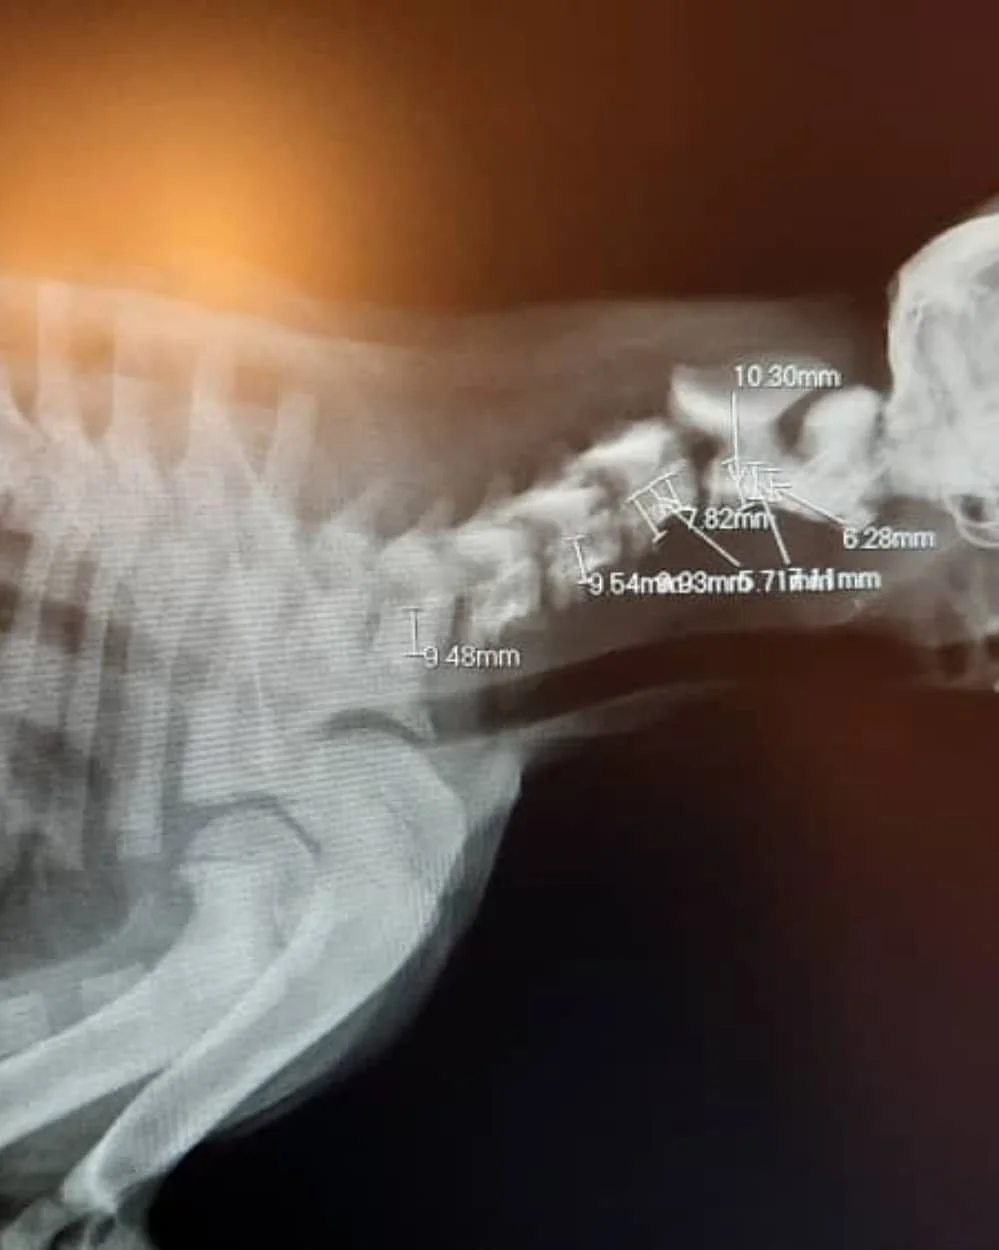

At the clinic, his condition was critical. The cervical vertebrae in his neck were fractured, leaving him in excruciating pain. Many debated euthanasia, fearing that survival was impossible and that keeping him alive would only prolong his suffering.

But the team chose hope. A skilled surgeon undertook an hours-long operation, carefully stabilizing his spine with plates and precision. It was a race against time, and against despair.

Surgeries like his are not just medical procedures — they are lifelines. Without immediate intervention, his broken neck would have meant certain death. Instead, he was given a second chance, a chance that came with enormous cost: advanced imaging, hours of specialized surgery, IV medications, antibiotics, and weeks of rehabilitation.